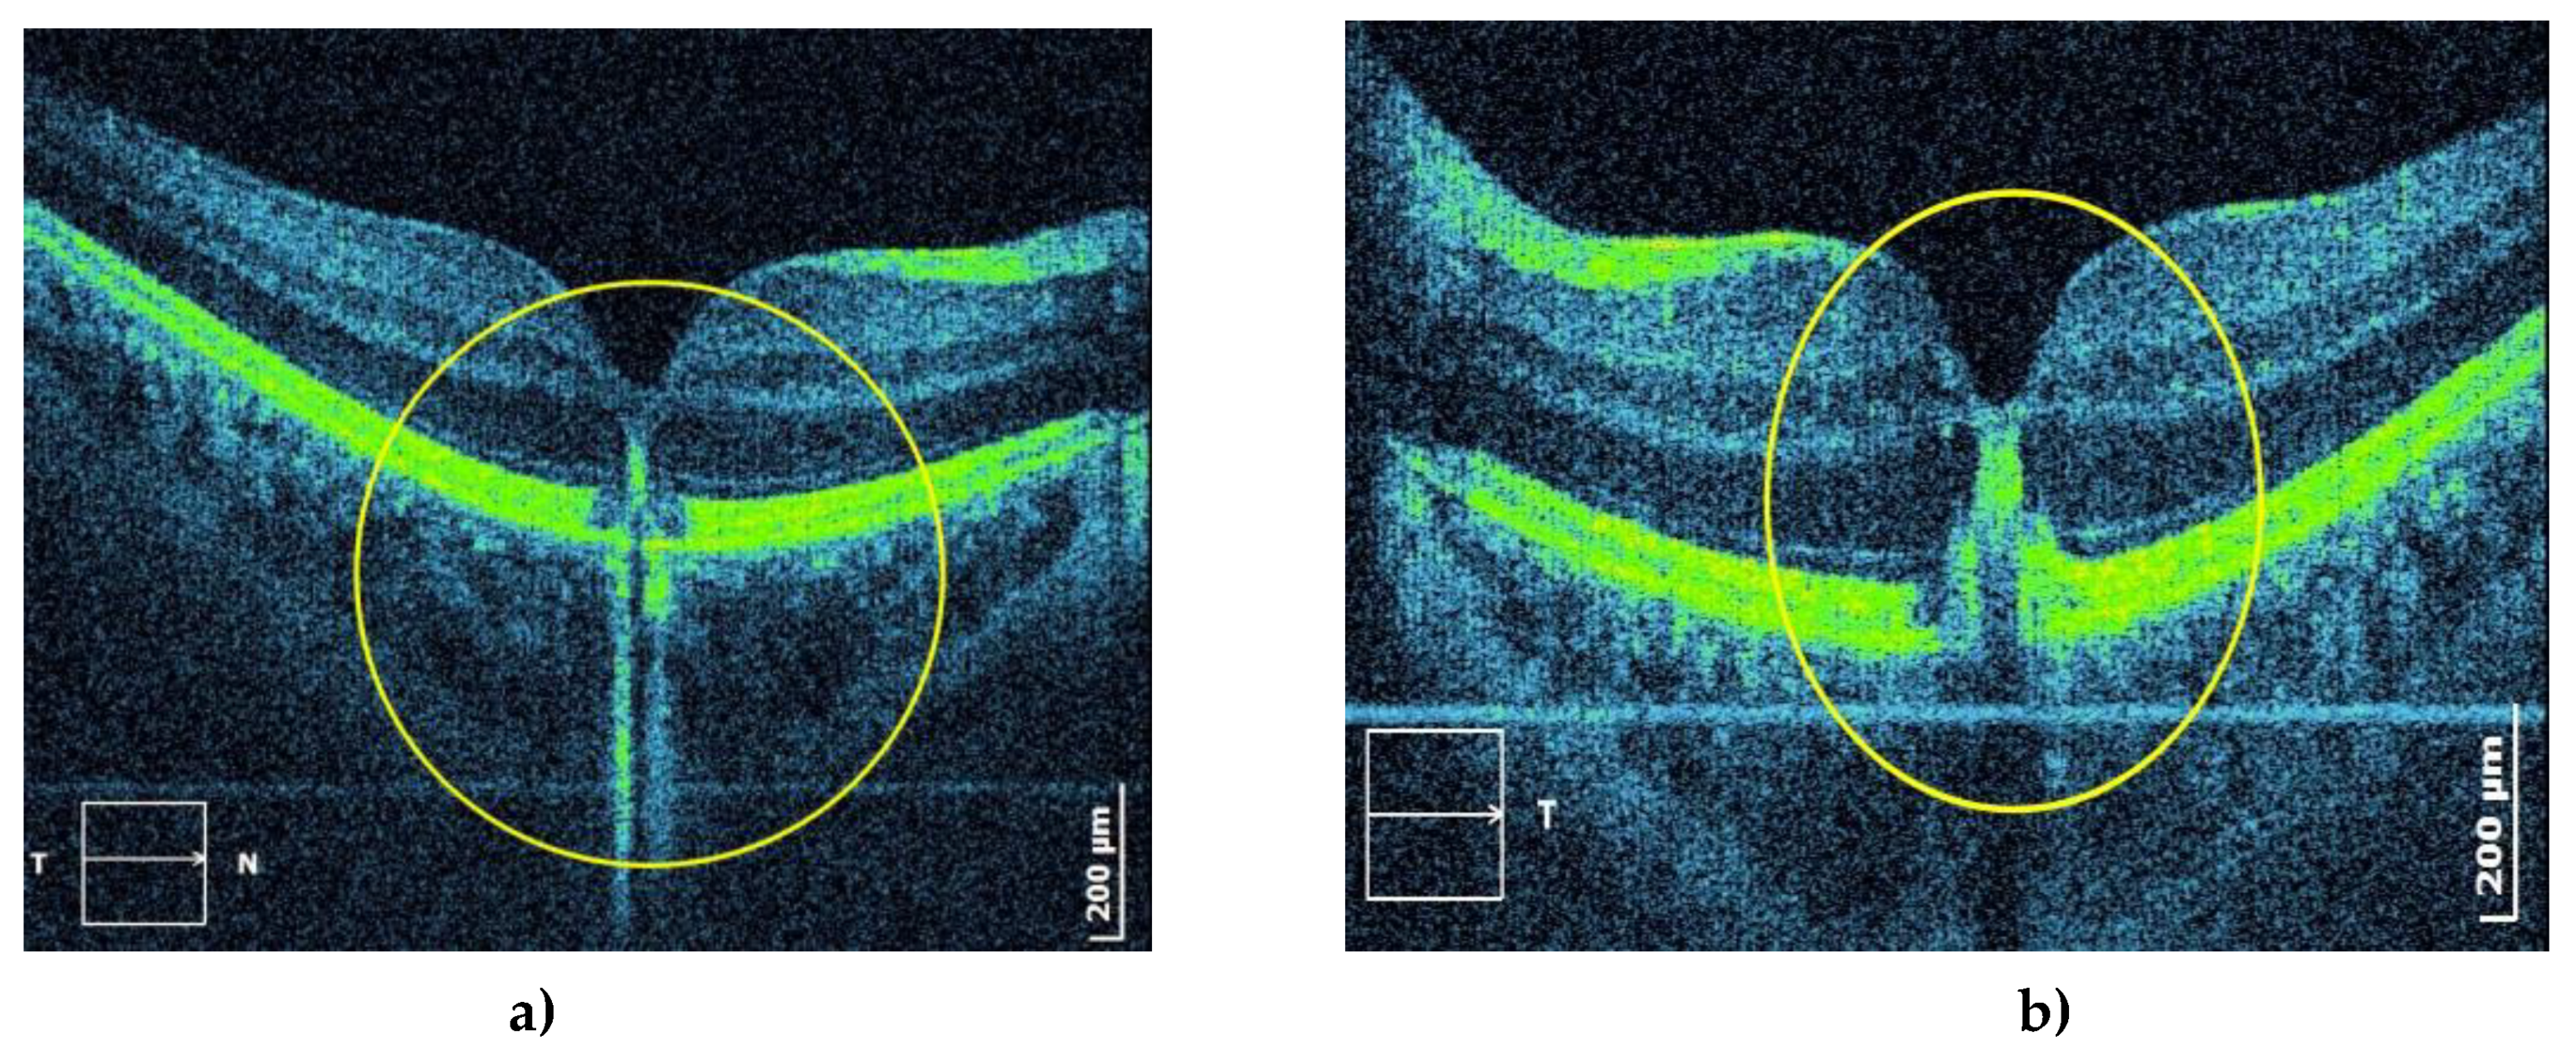

The first eye check-up revealed that the best-corrected visual acuity was 1.0 right and 1.0 left (on a LogMAR chart). An examination using the slit lamp only showed an incipient cataract on the posterior pole of the left lens and normal intraocular pressure. A fundus examination revealed a yellowish lesion in the macula’s center (Figure 2). Fundus autofluorescence (FAF) showed autofluorescent lesions in the corresponding place (Figure 3), whereas fluorescein fundus angiography (FFA) showed early fluorescence in the fovea due to the window effect and minor hypofluorescence (Figure 4). Optical coherent tomography (OCT) showed subfoveal, oval, dense deposits and disorders of the ellipsoid zone and external limiting membrane (Figure 5).

The eye check-up showed a decrease in visual acuity in both eyes. The best-corrected visual acuity was 0.8 right and 0.7 left (on a LogMAR chart). Examination with the slit lamp showed a normal anterior segment with normal intraocular pressure. A fundus examination revealed yellowish lesions located centrally in both maculae, with RPE changes in the right eye (Figure 9). The FAF showed oval autofluorescent lesions in the corresponding place (Figure 10), whereas the FFA showed a hypofluorescent blocking lesion centrally in the macula, surrounded by a narrow zone of early fluorescence due to the window effect (Figure 11). OCT showed subfoveal disorders of the RPE, a lesion of the ellipsoid zone, and external limiting membrane lesions, as well as deposits in the external layers of the macula (Figure 12).

The mentioned pathological processes could explain the changes in the macula of our patients. The described thickening may conform to the accumulation of metabolic products and non-phagocytosed outer segments of photoreceptors, which are usually phagocytosed in a physiological state. Outer segments of photoreceptors remain accumulated in the external layers of the retina due to dysfunction of phagocytosis and transport through the RPE. Damage to the RPE (seen as the window effect on FFA (Figure 4 and Figure 11) is attributed to iron overload in RPE cells and intercell spaces and degeneration of RPE cells, which could explain other components of the macular lesion. Structural changes are also visible as disordered continuity of the retinal pigment epithelium and migration of RPE cells (Figure 5 and Figure 12).

Figure 5. Optical coherent tomography (OCT) shows a three-dimensional subfoveal, hyperreflective lesion (yellow circles) in the outer layers of the macula in the right (a) and left (b) eye.

Figure 12. OCT shows damage to the RPE, deposits of hyperreflective material, and pigment migration toward the inner layers of the macula of the right (a) and left (b) eye.